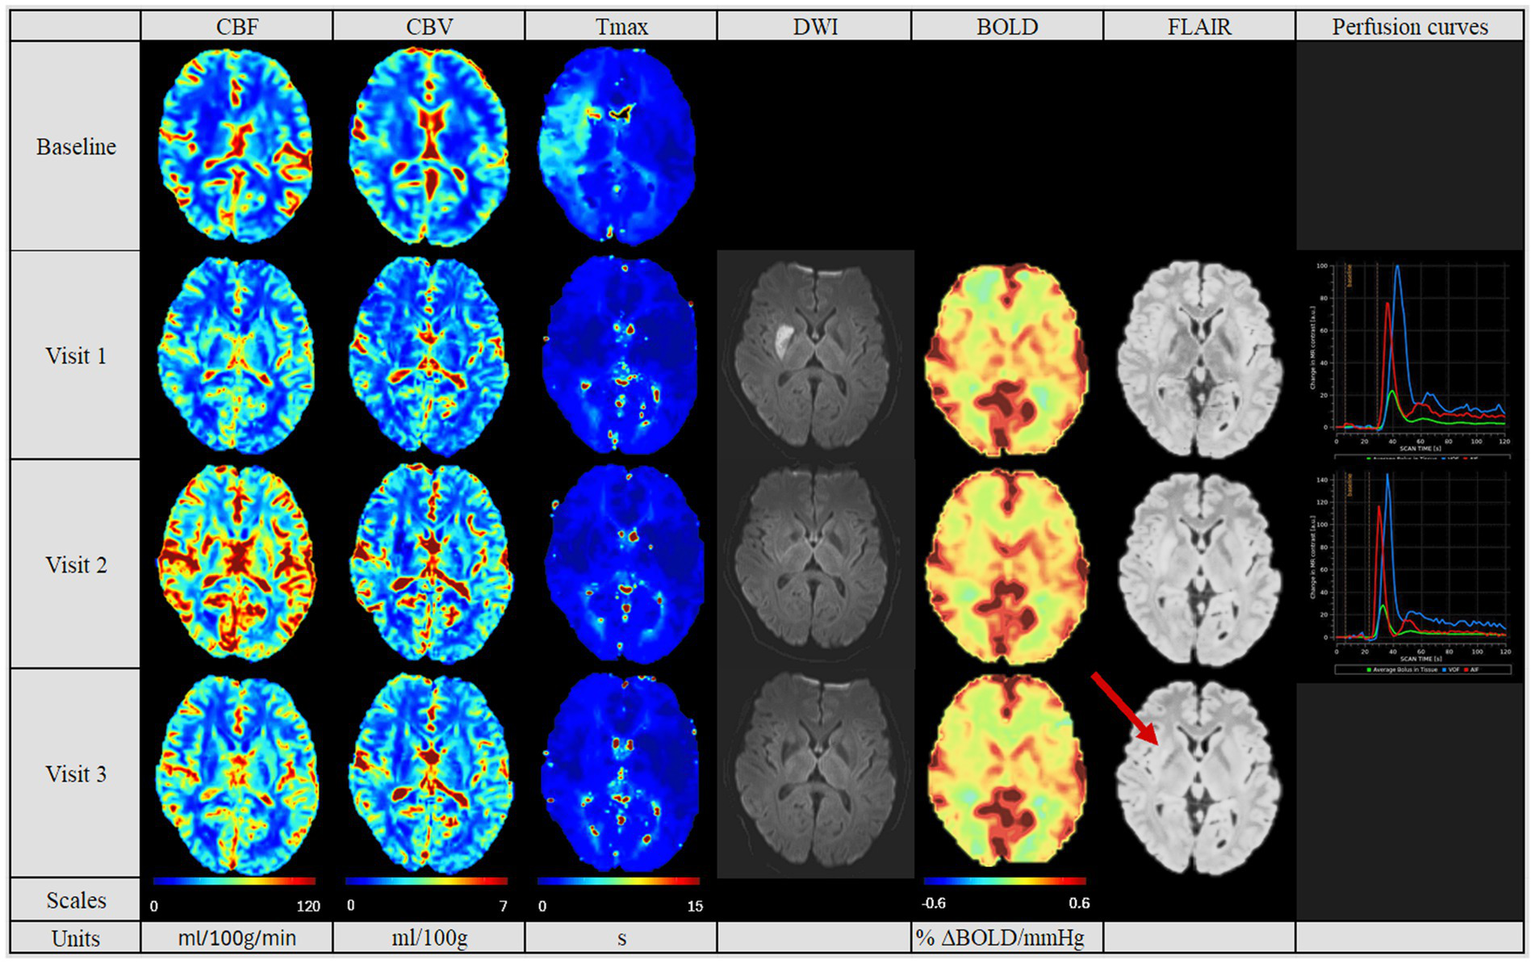

Figure 2

Perfusion pattern “normalized”. In this perfusion group, patients showed after MT similar CBF, CBV and Tmax values in both hemispheres. In addition, perfusion studies including BOLD-CVR, DWI and FLAIR modalities are shown. Finally, perfusion curves show the change in contrast agent over time, where the red line indicates the AIF, the blue line the VOF and the green line the average bolus in tissue (no V3 available). In this group, no perfusion dynamics could be observed. The FLAIR hyperintense signal showed the final lesion volume (indicated by the red arrow). Visit 1 was performed <72 hours, Visit 2 7 ± 2 days, and Visit 3 90 ± 14 days after onset. AIF: Arterial Input Fraction, BOLD-CVR: Blood Oxygenation-Level dependent Cerebrovascular Reactivity, CBF: Cerebral Blood Flow, CBV: Cerebral Blood Volume, DWI: Diffusion Weighted Imaging, FLAIR: Fluid Attenuated Inversion Recovery, MT: Mechanical Thrombectomy, Tmax: Time-to-Maximum, VOF: Venous Output Function.

In the follow-up PWI studies, the groups with the normalized perfusion after MT (Figure 2) retained their normalized perfusion pattern over all follow-ups. Similarly, for the hypoperfusion group (Figure 3), we observed a persistent circumscribed hypoperfused area without detectable changes in any follow-up. There was no case with later reperfusion. In contrast, the hyperperfusion group showed a tendency to develop a hypoperfusion in the initially affected hyperperfused area between visit two and three (7 days (+/− 2 days) and 90 days (+/− 14 days), see Figure 3), with respective decreased CBF, CBV and increased Tmax values.

The final infarct volume was estimated by quantifying lesion volume from the fluid-attenuated inversion recovery (FLAIR) at visit 3. A tendency for the largest infarct volumes were found in the hyperperfusion group, followed by the hypoperfusion group and the normalized group (35,278 cm3 [Q1–Q3 10,989–61,143], 11,276 cm3 [Q1–Q3 10,352–28,460 cm3] and 4,456.6 cm3 [Q1–Q3 1,493–12,660 cm3], respectively, p = 0.353, see Table 2). Also, we saw a tendency for a better collateral status for the “normalized” group, while this was the poorest for the hyperperfusion group (good status in normalized group for 6 (75%) patients, vs. 2 (33%) in hyperperfusion group, p = 0.657).

In Table 3 we summarized the results of the advanced perfusion studies with BOLD-CVR and NOVA. Within the BOLD-CVR analysis, we observed the highest values in the normalized group for the affected medial cerebral artery (MCA) region, while lower and even negative values were observed at visit one for the hyperperfusion group (0.12 [Q1–Q3 0.09–0.19] vs. − 0.01 [Q1–Q3–0.02-0.07], p = 0.049).